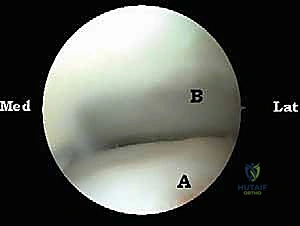

الخطوة 3: الاستكشاف البانورامي (Diagnostic Arthroscopy)

يتم إدخال كاميرا المنظار عالية الدقة (4K) عبر أحد المداخل، بينما تُستخدم الأدوات الجراحية الدقيقة في المدخل الآخر. تتيح الكاميرا للدكتور هطيف رؤية الهياكل الداخلية مكبرة عشرات المرات على شاشة عملاقة، مما يسمح بتقييم دقيق للمفاصل، الأوتار، والأربطة.